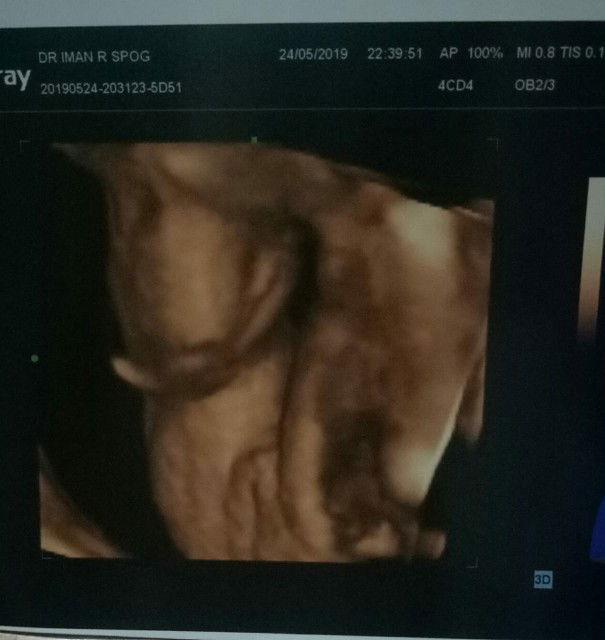

Malam bunda semua, saya mau tanya. Dari foto hasil USG ini apa benar itu uda fix baby nya cwe ya bun(itu pas kelaminya yg k foto) . Efek pengen punya baby cewe, krna anak ke 1&2 cowo. Takut nya nnti hasil usg nya brubah2. Soalnya ada d kelurga d usg smpe usia 9bln dokter blg cwe, tp ternyata pas lahir anak nya cwo

Sabar bunda.. byk yg g paham dg mksd pertanyaan bunda..😊 Tp kl mnrt sy itu hasilnya udh jls cwe.. jd kmungkin berubah kcil...

sepertinya iya bun, JK nya seperti bibir. dan terbelah di tengah.. selamat ya bun. semoga sehat selalu

Itu kan4D ya bund?kalo 4D kemungkinan salahnya lbh kecil.tp bukan brrt g bs salah..

Cewe bun. Kemarin aku usg posisinya juga sama kyk gitu, dan ada bolanya soalnya cowo

Saya hasil usg 4d kaya gitu dokter bilang cewek